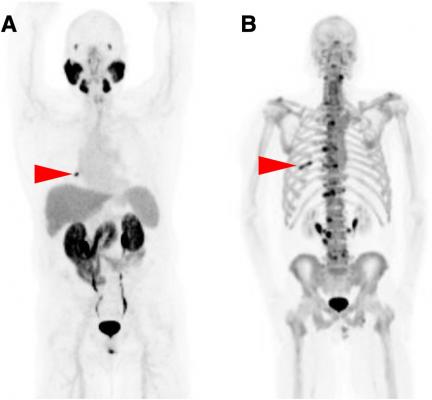

Multiparametric Magnetic Resonance Imaging For The Detection Of Clinically Significant Prostate Cancer What Urologists Need To Know Part 3 Targeted Biopsy European Urology

Multiparametric Magnetic Resonance Imaging For The Detection Of Clinically Significant Prostate Cancer What Urologists Need To Know Part 3 Targeted Biopsy European Urology from els-jbs-prod-cdn.jbs.elsevierhealth.com